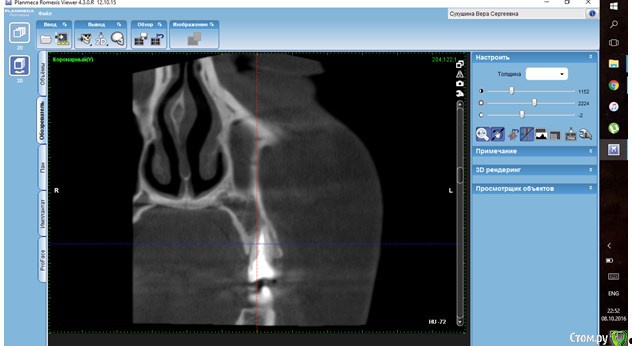

Verasss Опубликовано 8 октября, 2016 Автор Поделиться Опубликовано 8 октября, 2016 КТ от 08.09. Извините, что в таком виде, надо менять ОЗУ. Ссылка на комментарий

DmitrySH Опубликовано 8 октября, 2016 Поделиться Опубликовано 8 октября, 2016 В таком виде КТ малоинформативно. Но гайморита нет. Ссылка на комментарий

Verasss Опубликовано 28 октября, 2016 Автор Поделиться Опубликовано 28 октября, 2016 Добрый вечер! Ещё раз попытаюсь прикрепить скриншоты КТ от сентября. Если качество совсем не устраивает, подскажите, пожалуйста, какие сделать снимки?К сожалению, программа не позволяет вывести снимки на полный экран и заскриншотить в более хорошем качестве. Ссылка на комментарий

Verasss Опубликовано 28 октября, 2016 Автор Поделиться Опубликовано 28 октября, 2016 еще снимки Ссылка на комментарий

Verasss Опубликовано 28 октября, 2016 Автор Поделиться Опубликовано 28 октября, 2016 и еще Ссылка на комментарий